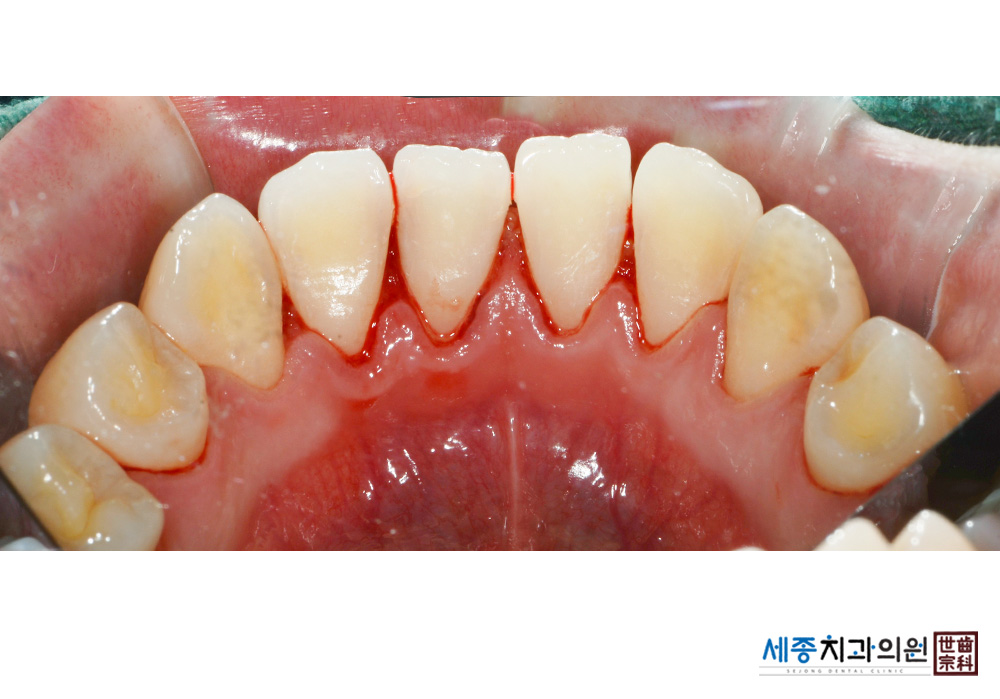

[스케일링] 치주질환 예방 스케일링

치료후 : 2020-03-02

가글마취&저주파 스켈러를 사용한 스케일링